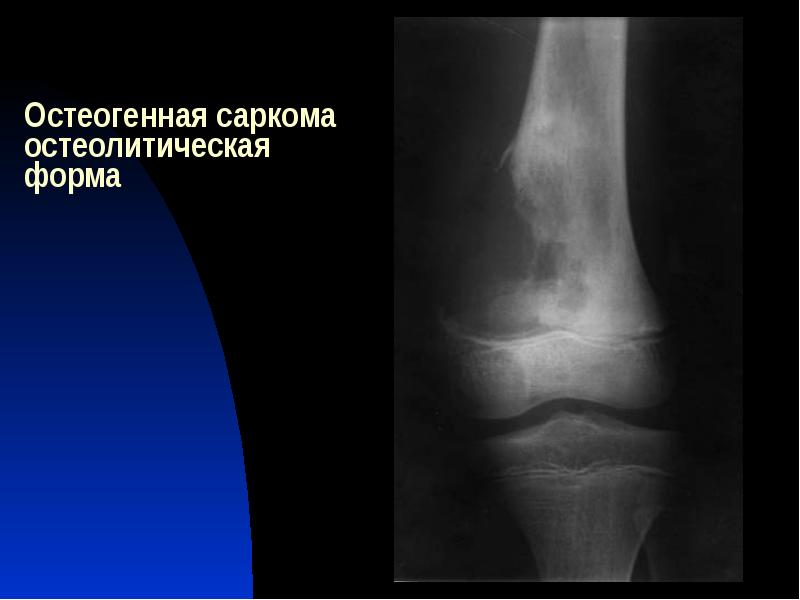

Рентгенологическая картина остеогенной саркомы кости - 98 фото